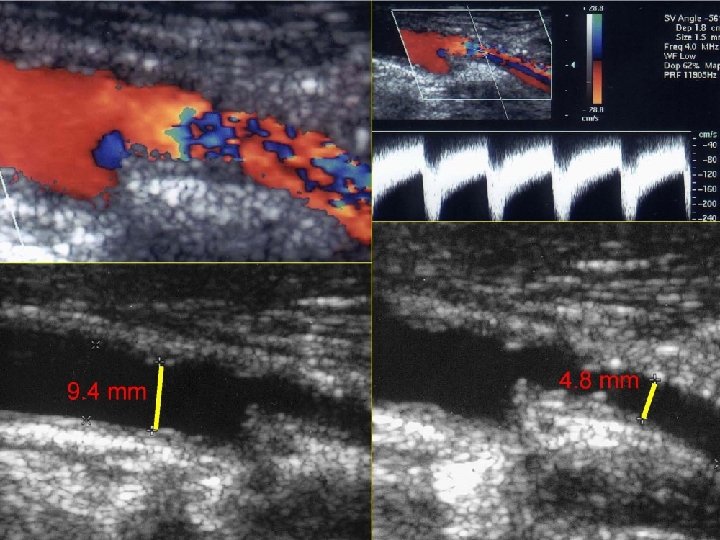

• MISMATCH CCA-ICA

EMBOLΟGENIC LESIONS • Soft plaques • Ulcerated lesions • Thrombotic material

EMBOLΟGENIC LESIONS

EMBOLIGENIC LESIONS • CONSIDERATIONS - Most emboli occur during stent-placement and postdilatation - 40% stroke after the procedure • STENTS REQUIREMENTS - Good wall coverage - Capturing of emboligenic material - Avoid plaque protrusion • CHOICE Closed-cell design